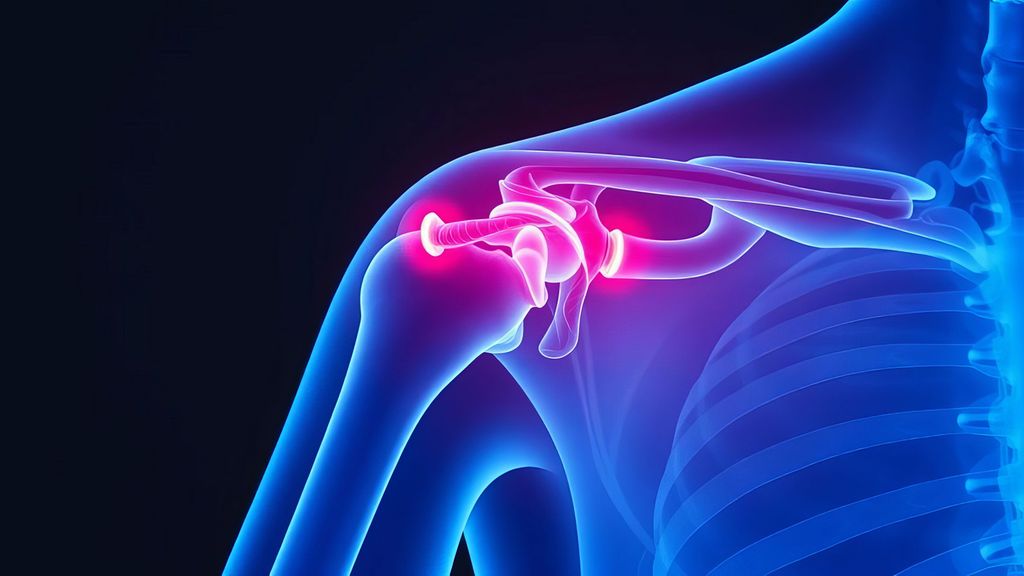

Verletzungen des Akromioklavikulargelenks (ACG) gehören zu den häufigsten Schulterverletzungen bei jungen und aktiven Menschen, insbesondere auch aufgrund der zunehmenden Beliebtheit von ...